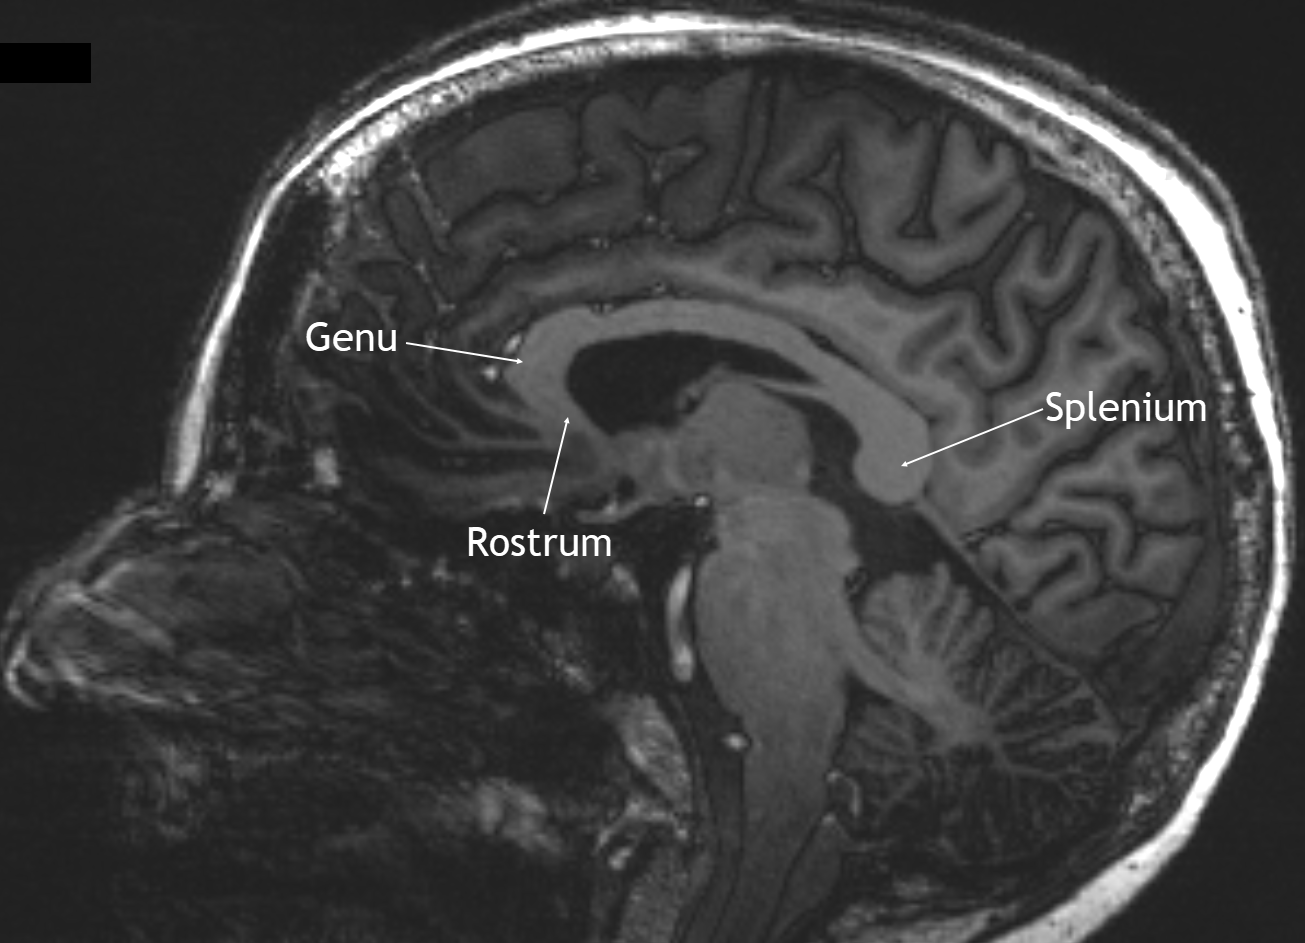

Bildgebung

Darstellung des Corpus callosum mit seinen verschiedenen Abschnitten im sagittalen 7 Tesla MRI in einer T1 Sequenz mit Kontrastmittel.

Corpus callosum im MRI